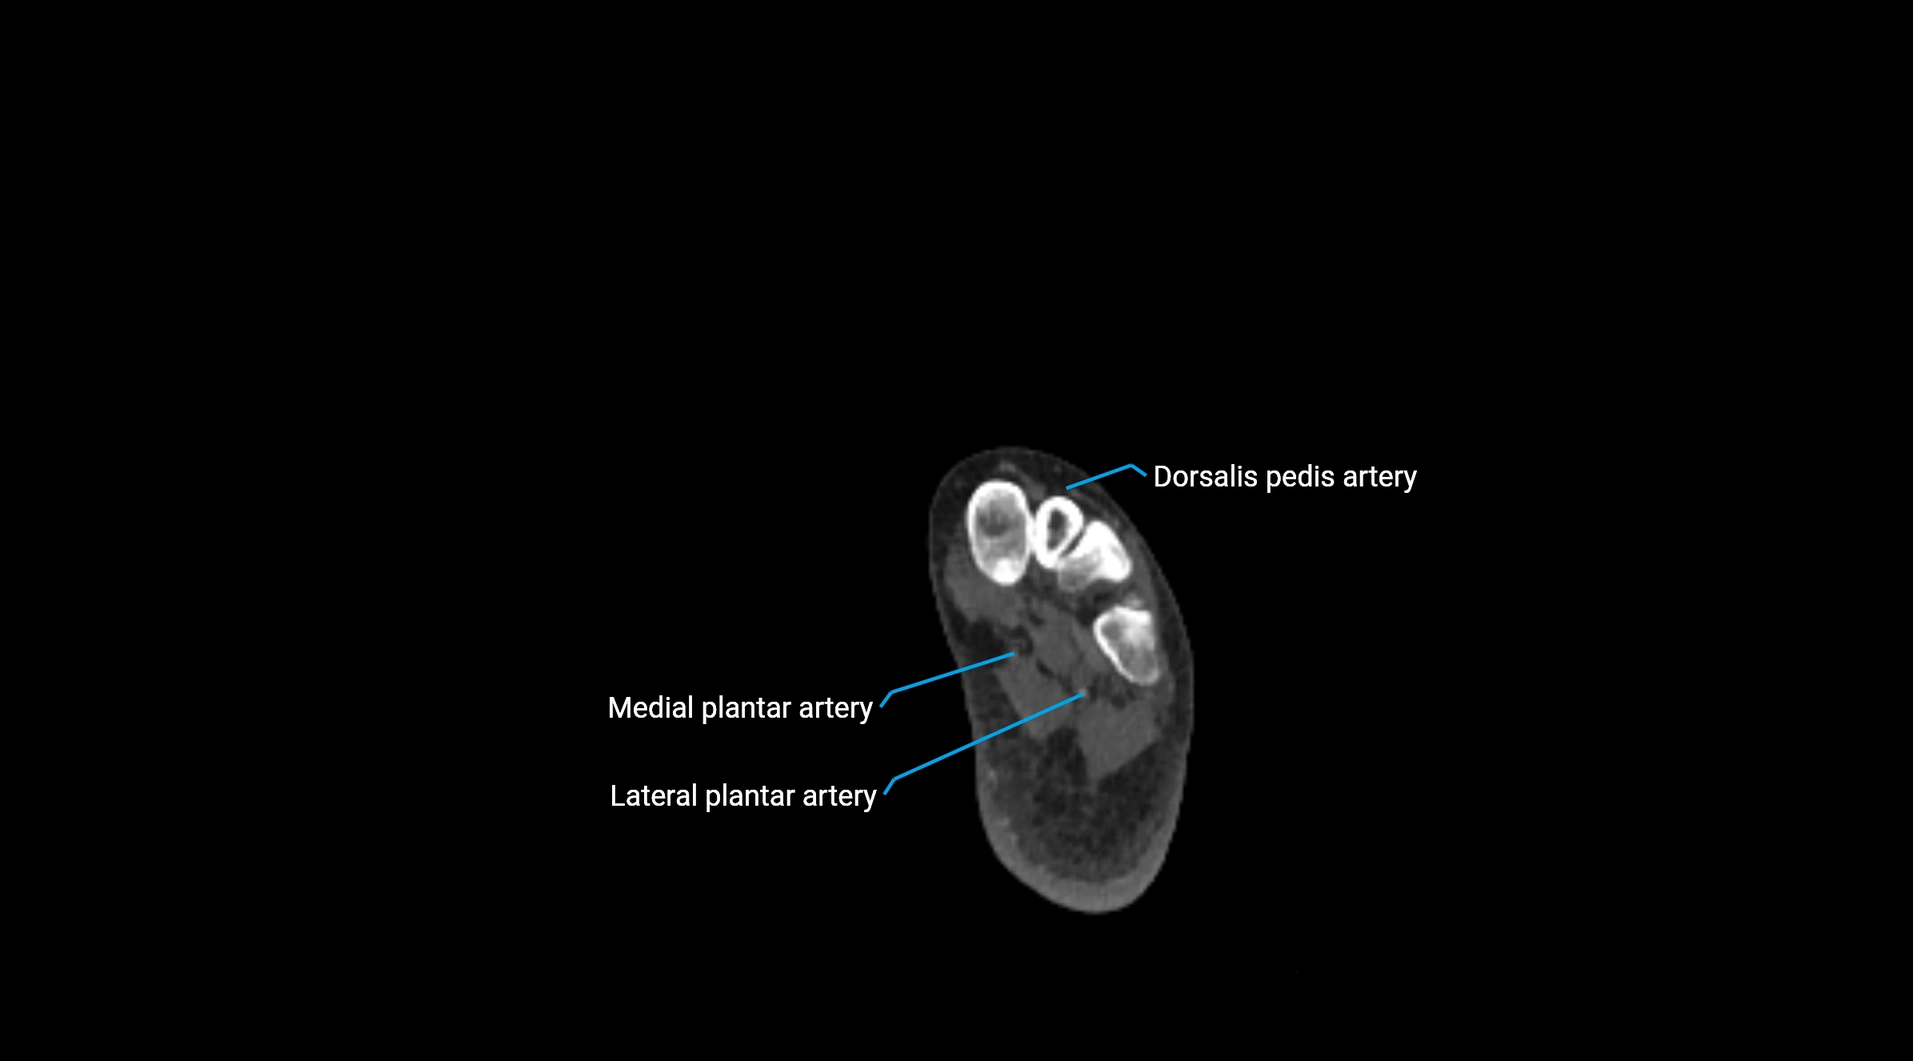

CT images

image

Contrast-enhanced CT (CTA):

• Gold standard for abdominal aortic imaging

• Provides excellent detail of lumen, wall, aneurysm, thrombus, and branch vessels

• Multiplanar and 3D reconstructions help in aneurysm measurement, stent graft planning, and dissection evaluation